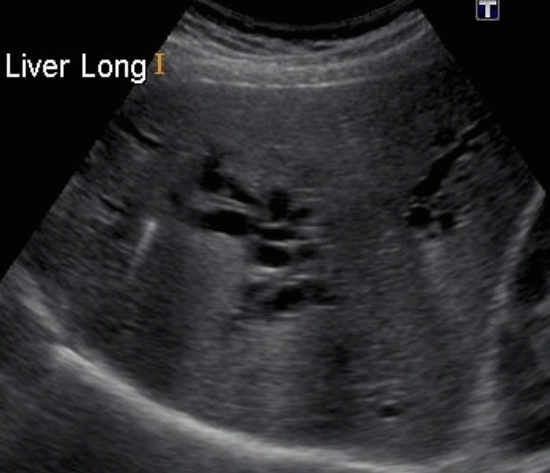

US finding

- 간내담관은 확장되고 간외담관은 정상이다.

- 담낭은 위축되며, 간외담관은 담즙 흐름이 없는 담관으로 묘출된다.

- 폐쇄된 담관부위에 종양의 윤곽이 보일 수 있으나 초음파상 발견하기 어렵다.